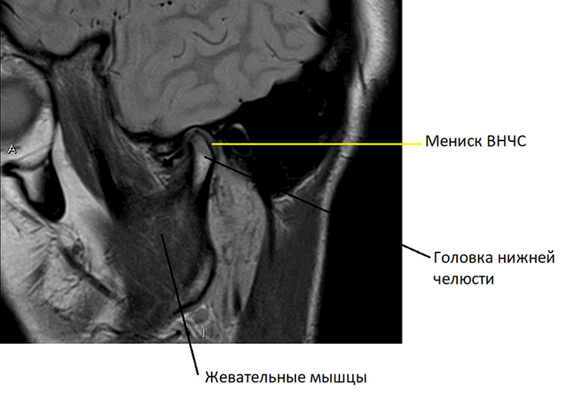

На серии таких снимков, сделанных послойно в виде тонких срезов в нескольких плоскостях, легко распознать суставные хрящи, покрывающие головки нижней челюсти и суставной бугорок, образующие височно-нижнечелюстной сустав, мениск ВНЧС. Видны отдельные связки и сухожилия, жевательные мышцы. Любое возможное патологическое изменение, такое как воспаление сустава или новообразование, тут же будет видно на МРТ.

Косо-сагиттальная проекция с закрытым ртом. Нормальный ВНЧС.

Суставной диск не дислоцирован, задняя его часть находится на 12 часах циферблата мыщелка.